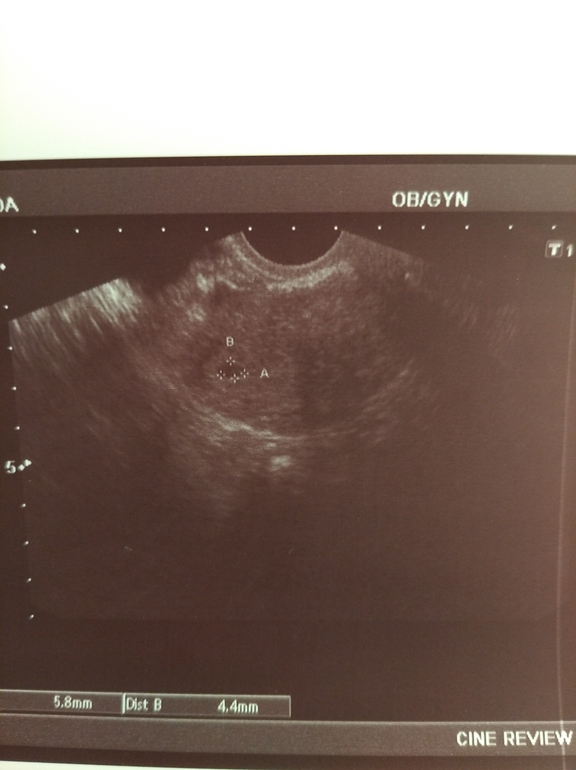

Девочки, нашли мою бубочку там где надо

☺️ Беременность маточная!!! Даже фото дали)))

Сегодня как раз день х. Я не знаю как узистка смогла найти, но она волшебница))

Она только поставила датчик на живот и сказала- вот оно, все на месте. Я прям там на кушетке и расплакалась. Потом посмотрела ещё раз вагинально - эндик 11,3 матка увеличена. В заключении написала беременность раннего срока? Но я то знаю что это мое чудо!

5,8×4,4 ми

Воронеж

С результатом хгч день назад в 97 и уже сегодня на узи ПЯ 5.8х4.4 ,да ещё абдоминальным датчиком !?